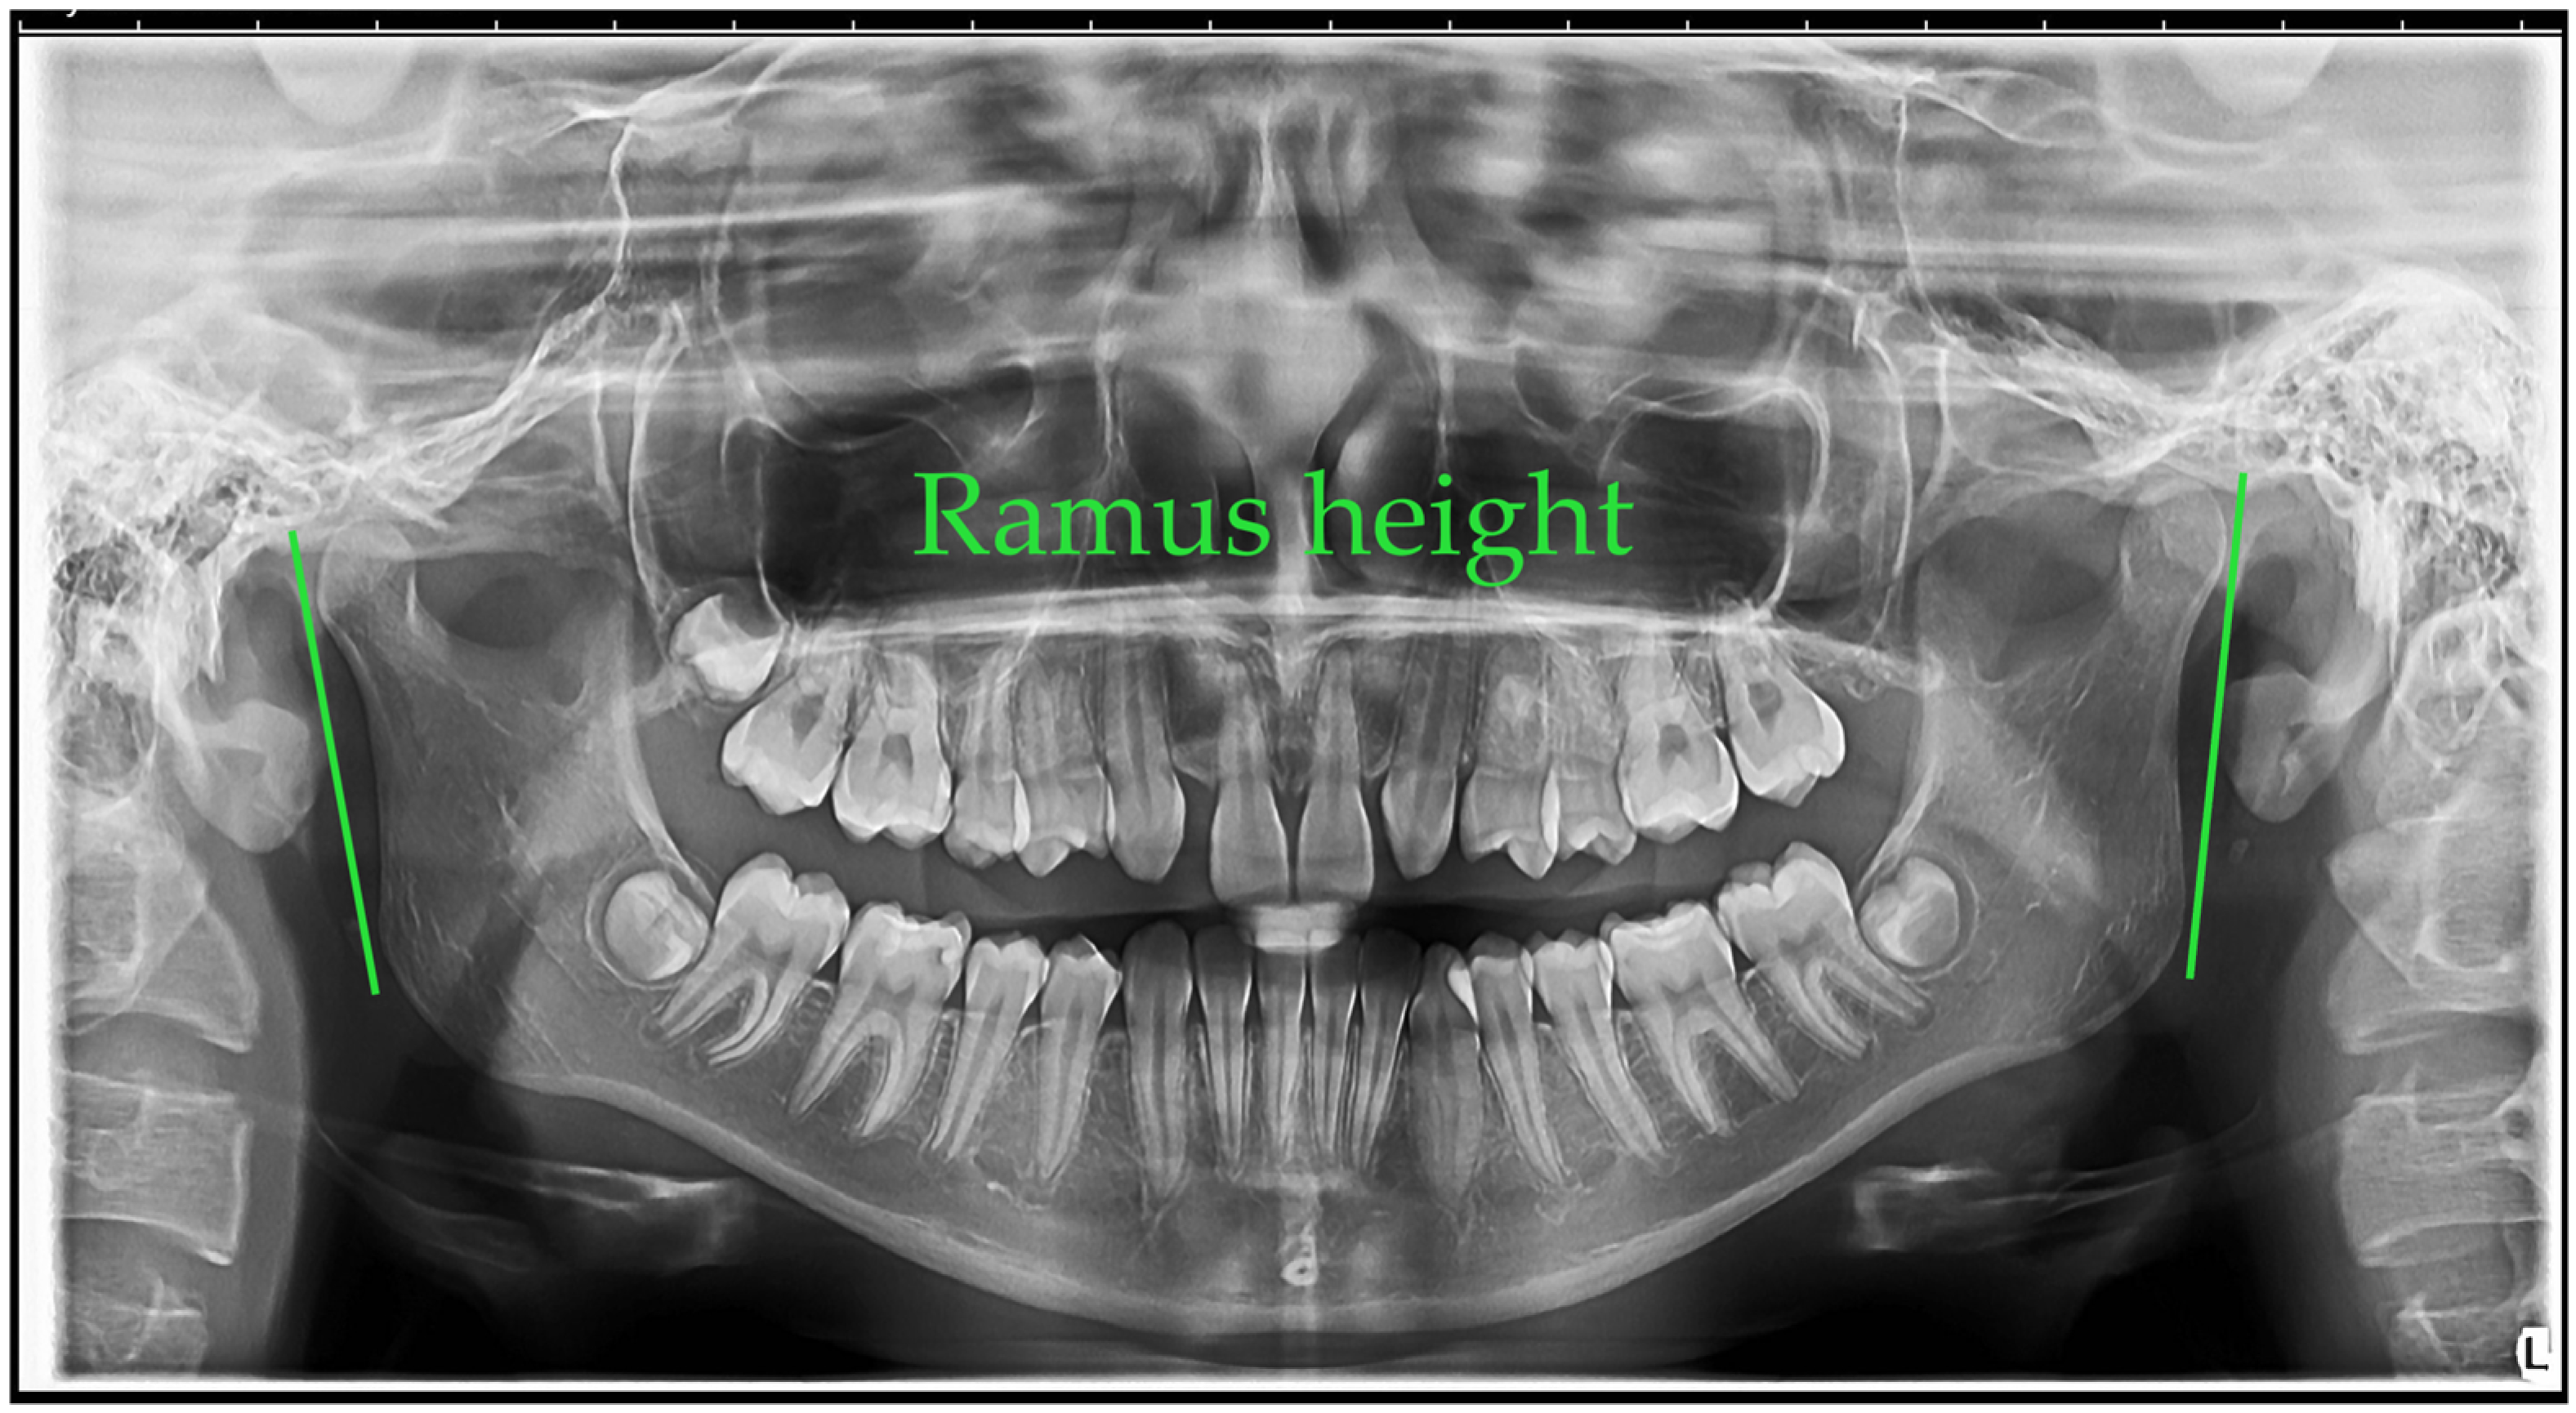

Figure 1, Figure 2, Figure 3, Figure 4, Figure 5 and Figure 6 illustrate the AI-assisted digital measurements exported from the WebCeph software, showing the identification of anatomical landmarks and linear or angular dimensions analyzed in this study.

Orthopantomogram illustrating the measurement of right and left mandibular ramus heights. The ramus height was defined as the linear distance from the most superior point of the mandibular condyle to the lowest point on the inferior border of the mandible, shown by the green lines. Measurements were recorded bilaterally for comparative analysis (Figure 3).

Figure 3. Bilateral Ramus Height Measurement on OPG. Co (condylion)—the most superior point on the mandibular condyle; Inf—the most inferior point on the mandibular border. The green line (Co–Inf) denotes ramus height measured bilaterally for comparative analysis. Note: Images represent direct screenshots exported from the WebCeph® AI platform. Landmarks and measurement lines were automatically generated and manually verified by the authors.